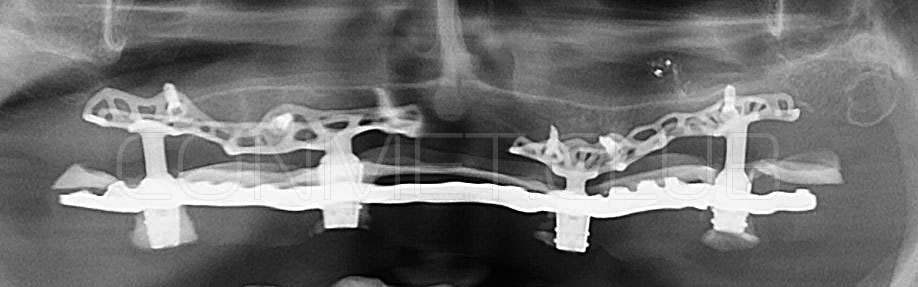

2. После этого произвели компьютерное моделирование самого имплантата и фиксирующих элементов. Примечательно, что в абатментах, использовался отлично зарекомендовавший себя и проверенный десятилетиями интерфейс КОНМЕТ! В результате получили несколько специальных файлов, позволяющих не только сделать сам имлантат, но еще до операции изготовить и сами зубы. Данные файлы передали в изготовление на специальном 3D оборудовании.

Имплантат напечатали из особого, биосовместимого, медицинского титана на предприятии имеющим соответствующую медицинскую лицензию. Толщина имплантата составила 0,8 мм, а вес всего несколько грамм!

Посмотрите на небольшом клиническом примере новый подход к конструированию имплантата по сравнению с имплантатами описанными в начале этой статьи.

Для просмотра проведите курсором мыши по изображению имплантата